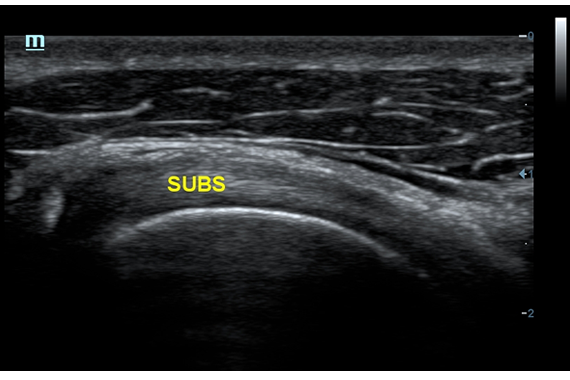

Система ультразвукового исследования Mindray DC-60 EXP X-INSIGHT является новейшей разработкой для проведения комплексных обследований на высшем уровне. Она обеспечивает решение самых сложных задач в таких областях, как кардиология, акушерство и гинекология, сосудистые заболевания, педиатрия и многие другие.

DC-60 EXP X-INSIGHT - это современный стационарный УЗИ-аппарат с функцией сенсорного управления и очищенной гармонической визуализацией, обеспечивающей лучшее контрастное разрешение и технологию 4D-визуализации. Он оснащен 21,5-дюймовым монитором, который может поворачиваться на 180 градусов, что удовлетворяет потребности врачей в качественной ультразвуковой диагностике.